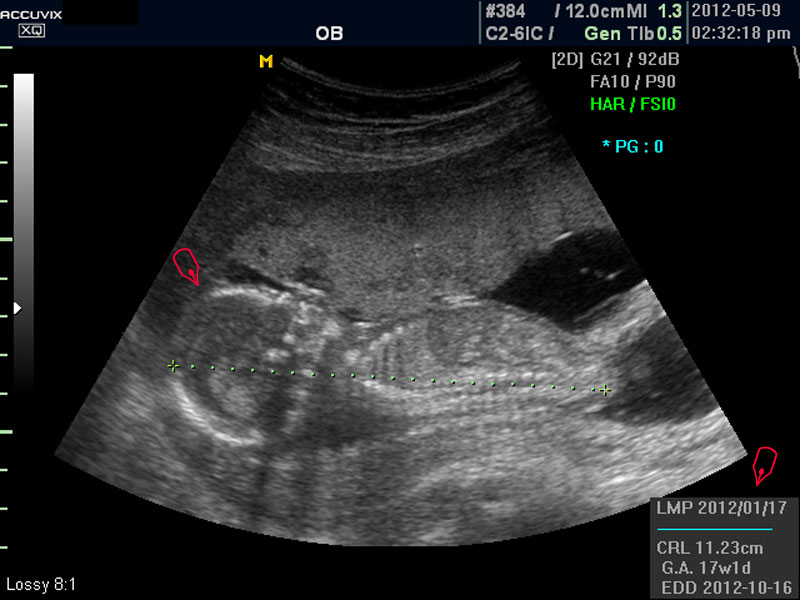

보통 태아의 발육은 머리부터 엉덩이까지의 크기인 CRL(Crown Rump Length의 약자)이 정상인가 하는 것과 태아의 두상 크기인 BPD(BiParietal Diameter의 약자)가 정상 범위에 들어 있는가 하는 것으로 판단합니다.

대신 첫번째 사진에서 보는 것처럼 태아의 전체 모습 특히 태아의 등쪽이나 복벽의 이상은 없는지 신경관 결손 등으로 인한 종괴가 있지는 않은지 관찰하며 태아의 복벽이나 등쪽은 일직선으로 매끈하게 보이는 것이 정상입니다.

첫번째 사진에서는 하지 부분은 대퇴부만 일부 보이며 이는 태아가 다리를 구부리고 있고 팔도 이리저리 움직여 머리 위나 목 쪽으로 두는 경우가 많아서 한번에 전체 모습을 찍기가 어려운 경우가 많습니다.

따라서 부분 부분 살펴 보면서 해당 모습을 찍어서 저장하거나 인쇄하여 드리기도 하는 것이며 아래 사진은 태아의 다리 부분을 찍은 것입니다.

모든 사진에서 우측 하단에는 기본적인 발육 정보가 기록되는데 세번째 사진에서 빨간 펜으로 표시한 부분이며 그 내용의 의미는 아래와 같습니다.

2. CRL

위에 말한 태아 크기를 말하는 지표로 실제 수치가 표시됩니다.

3. GA

Gestational Age의 약자로 우리말로는 임신 주기라고 하며 CRL이나 BPD등을 기준으로 했을때 임신 몇주 며칠에 해당하는 지 나타낸 것입니다.

5.EDD

Estimated Due Date의 약자로 초음파 측정치를 바탕으로 산출한 출산 예정일입니다.